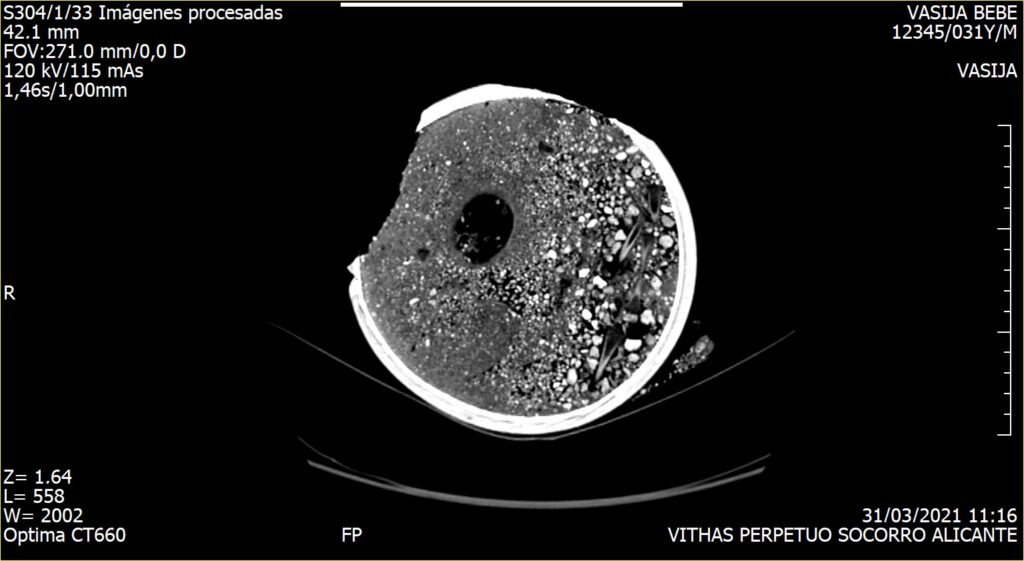

Debido a la fragilidad de los huesos se planteó la posibilidad de realizar un estudio radiológico que permitiría obtener la imagen del interior de la olla sin necesidad de ser excavada.

Este estudio, pionero en este tipo de enterramientos, fue realizado por el Hospital Vithas Alicante, quien puso a disposición de los arqueólogos, los mejores profesionales y los medios técnicos más avanzados para la consecución con éxito de esta tomografía computarizada aplicada a la Arqueología. Las pruebas practicadas revelaron que el cuerpo del perinatal se adaptaba a las paredes de la olla y que el cráneo se encontraba fracturado, quedando ambas partes solapadas.